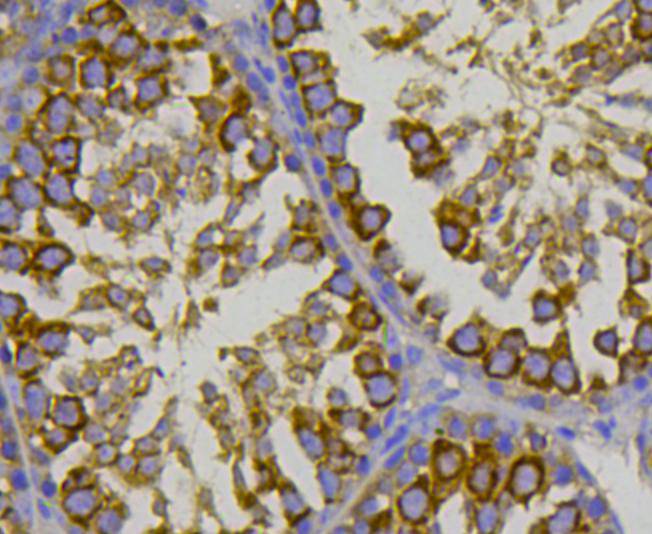

Immunohistochemical analysis of paraffin-embedded human breast cancer tissue using anti-HSP70 antibody. Counter stained with hematoxylin.

Immunohistochemical analysis of paraffin-embedded mouse testis tissue using anti-HSP70 antibody. Counter stained with hematoxylin.

Immunohistochemical analysis of paraffin-embedded mouse prostate tissue using anti-HSP70 antibody. Counter stained with hematoxylin.